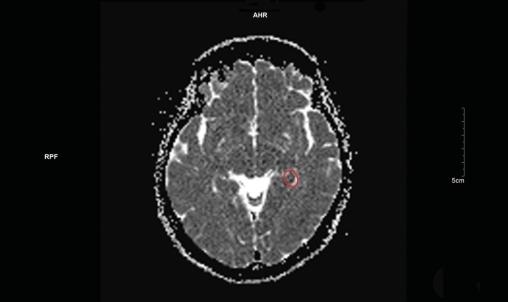

Une imagerie par résonance magnétique (IRM) cérébrale est réalisée quarante-huit heures après l’épisode, mettant en évidence un hypersignal punctiforme en séquence diffusion (fig. 1) et en hyposignal ADC (apparent coefficient diffusion) [fig. 2] localisé à la partie interne du lobe temporal gauche.

L’IRM permet de mettre en évidence les signes caractéristiques à la partie interne du lobe tempo­ral (hypersignal diffusion et hy­posignal ADC), avec une détection optimale deux et trois jours après l’épisode. Il est important de préciser au radiologue la nécessité de réaliser des coupes fines de la région.